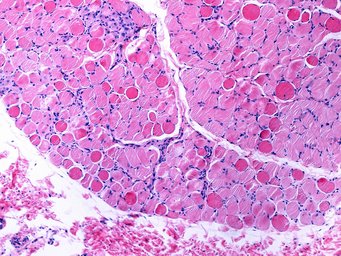

Duchenne muscular dystrophy (DMD) is a severe type of muscle disorder predominantly affecting boys. The disease is chronic and begins in childhood. The life expectancy of affected patients is significantly reduced. The disease, for which there is currently no cure, is caused by mutations in the dystrophin gene, which is located on the X chromosome. Dystrophin is important for cell membrane stability in muscle fibres. Due to the genetic defect, dystrophin is absent in these patients. As a consequence, muscle cells are restricted in their function and the musculature is increasingly weakened.